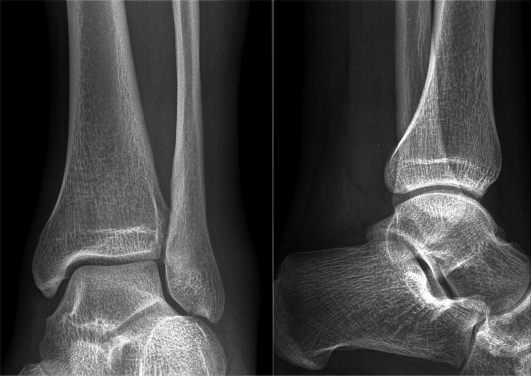

Разница в рентгенологических картинах:

- при артрозе плотность костной ткани повышается (остеосклероз), по краям суставных площадок образуются наросты-остеофиты, на фоне остеосклероза возможны единичные кистоподобные полости, окруженные склерозированным ободком;

- при артрите плотность кости уменьшается (остеопороз), формируются краевые дефекты костной ткани и множественные кисты.

Если данные лабораторных анализов указывают на артрит, а рентгенологическая картина характерна скорее для артроза, но имеет нетипичные черты, диагностируют артрозоартрит. В МКБ 10 такого заболевания нет, данный диагноз используется только в клинической практике.